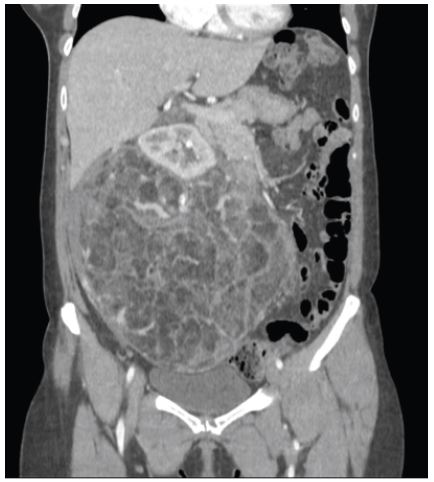

Patient A presented to the Emergency department with two episodes of presyncope, which were subsequently associated with intense abdominal pain. An abdominal tumor was palpated. The abdominal x-ray showed a large mass that had displaced the bowel (Figure 1). CT findings compatible with Wunderlich syndrome were additionally observed in patient A, although there was no evidence of active bleeding (Figure 2). Given the size of the lesion and the high risk of bleeding in this patient, an open partial nephrectomy was performed. A midline laparotomy revealed a large mass that was excised under arterial clamping with a total ischemia time of eight minutes (Figure 3). The weight of the surgical specimen was 2480 grams (Figure 4). The surgical procedure lasted 3 hours and we transferred and two units of red blood cells were subsequently transfused. On the 8th day, peritoneal drainage was removed, and patient was discharged.

Figure 1: The abdominal x-ray reveals the displacement of the bowel loops into the left hemiabdomen.

Figure 2: CT scan of patient A shows an AML with a maximum diameter of 24,5cm.